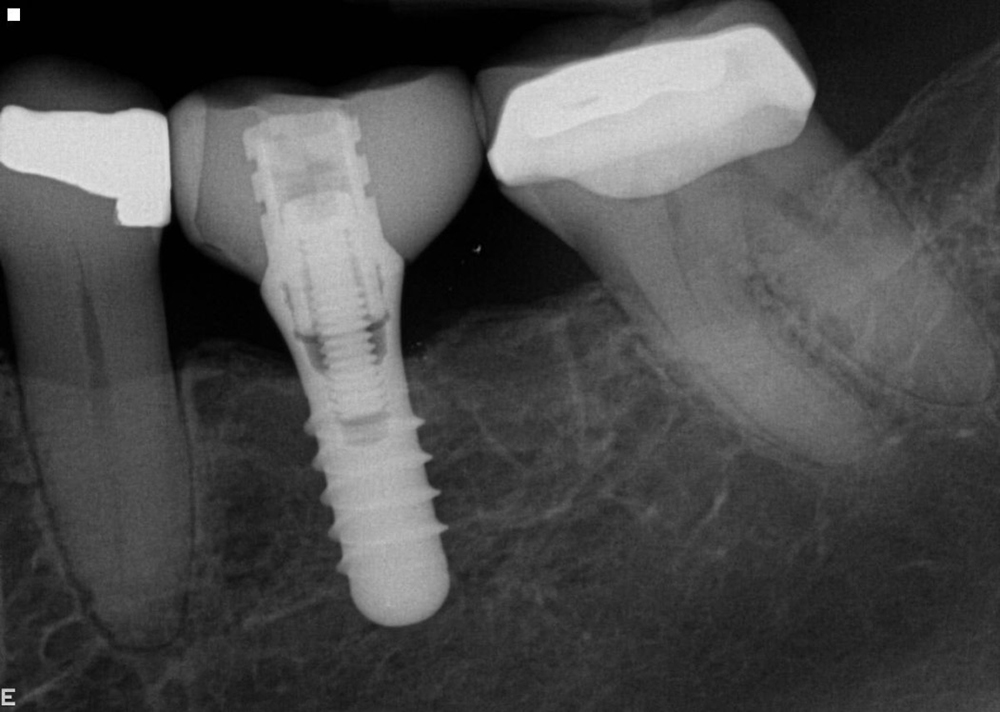

Tooth no. 19 was isolated with a dental dam under local anesthesia. All existing restorative material and decay was excavated leaving a very evident crack into the pulp, down to the pulpal floor. The mesial canals were completely calcified, the decay extended beyond the bone level. This tooth was diagnosed as hopeless and scheduled for removal. A provisional was placed at this appointment.

Tooth no. 30 was deemed hopeless at initial evaluation and extracted.